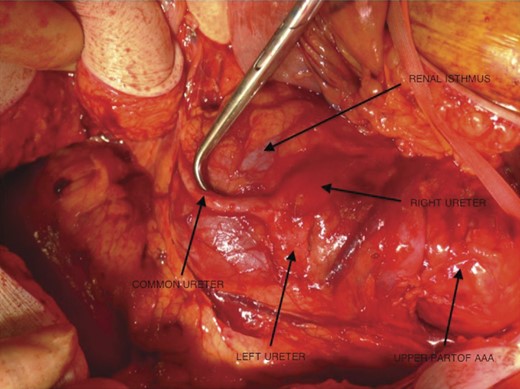

Computed tomography scan done revealed bilobed juxtarenal AAA measuring ∼6.7 cm in transverse diameter, but no leaks or ruptures were reported. An open AAA repair was done and a HSK was found with both ureters uniting over the renal isthmus forming a common ureter that continued down to the urinary bladder (Figs 1–6). Although the patient died from complications of the surgery, the authors wish to discuss the presence of fused ureters in a patient with HSK.

The left and right ureters running over the renal isthmus and fusing to form a common ureter.

The upper part of the aortic aneurysm, the left and right ureters running over the renal isthmus and fusing to form a common ureter (been pushed by the surgical instrument).